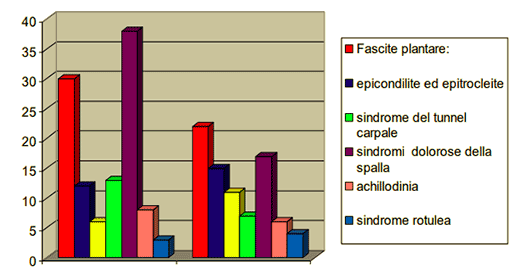

Li abbiamo divisi per patologia in 7 gruppi costituiti da uomini e donne con un età compresa tra i 17 e i 87 anni in questo modo:

Fascite plantare: 30 donne e 22uomini

epicondilite ed epitrocleite: 12 donne e 15 uomini

cocxalgia: 6 donne e 11 uomini

sindrome del tunnel carpale: 13donne e 7 uomini

sindromi dolorose della spalla: 38 donne e 17 uomini

achillodinia: 8donne e 6 uomini

sindrome rotulea: 3donne e 4 uomini